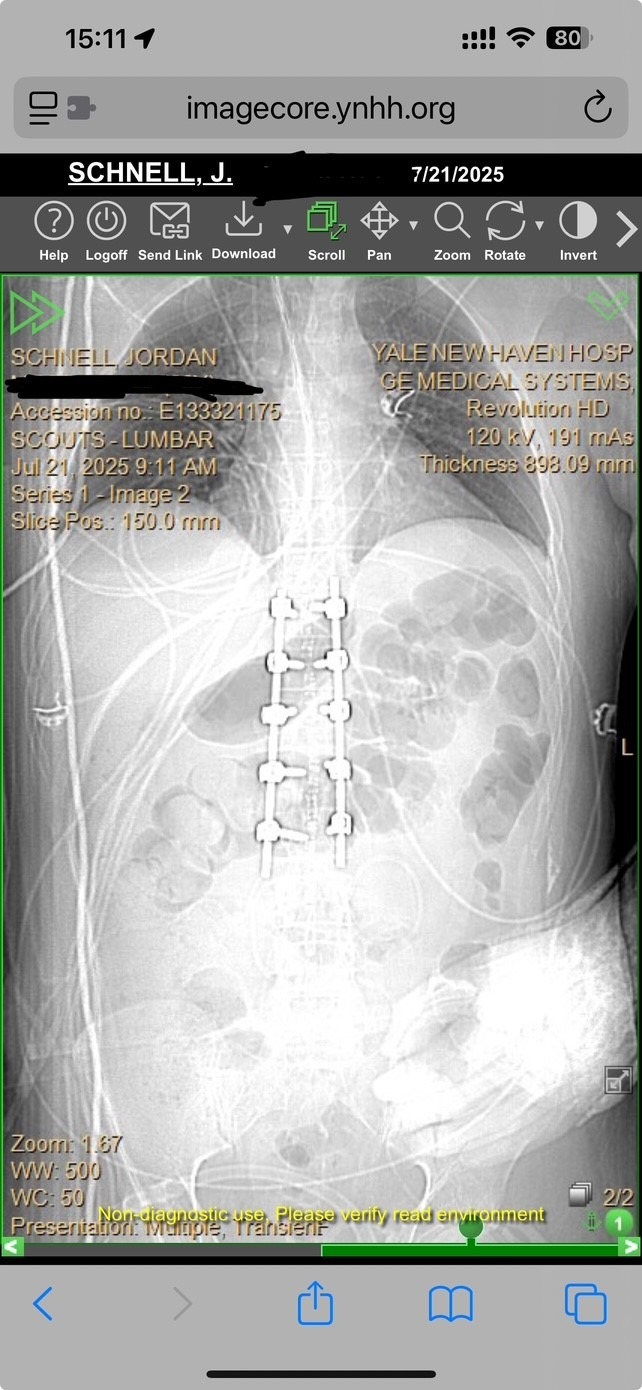

On the night of July 18, 2025, my stepson Jordan Schnell and my husband Will Schnell were riding their motorcycles home from visiting Will's mom on I-91 South in Connecticut when a car with its lights off hit Jordan from behind, threw him from his bike onto the highway, ran him over, and then fled the scene, dragging Jordan’s bike under the car’s front end for nearly a mile. As of July 22, the driver still has not been apprehended. It is a miracle that Jordan survived. But he was severely injured, suffering shattered and fractured vertebrae, a fractured pelvis, broken ribs, a broken clavicle, a broken arm, a fractured wrist, internal bleeding, and other injuries. He will be in the hospital for a month undergoing multiple surgeries, and then will likely face months in a rehabilitation facility to heal. His surgeons estimate his total recovery and healing time to be at least 2 years. Our family would deeply appreciate donations of any amount to help Jordan with his significant medical and physical rehabilitation expenses. We are profoundly grateful that Jordan is alive, and profoundly grateful for any help you might be able to provide. Thank you from the bottom of our hearts. -Gretchen Sullivan & family